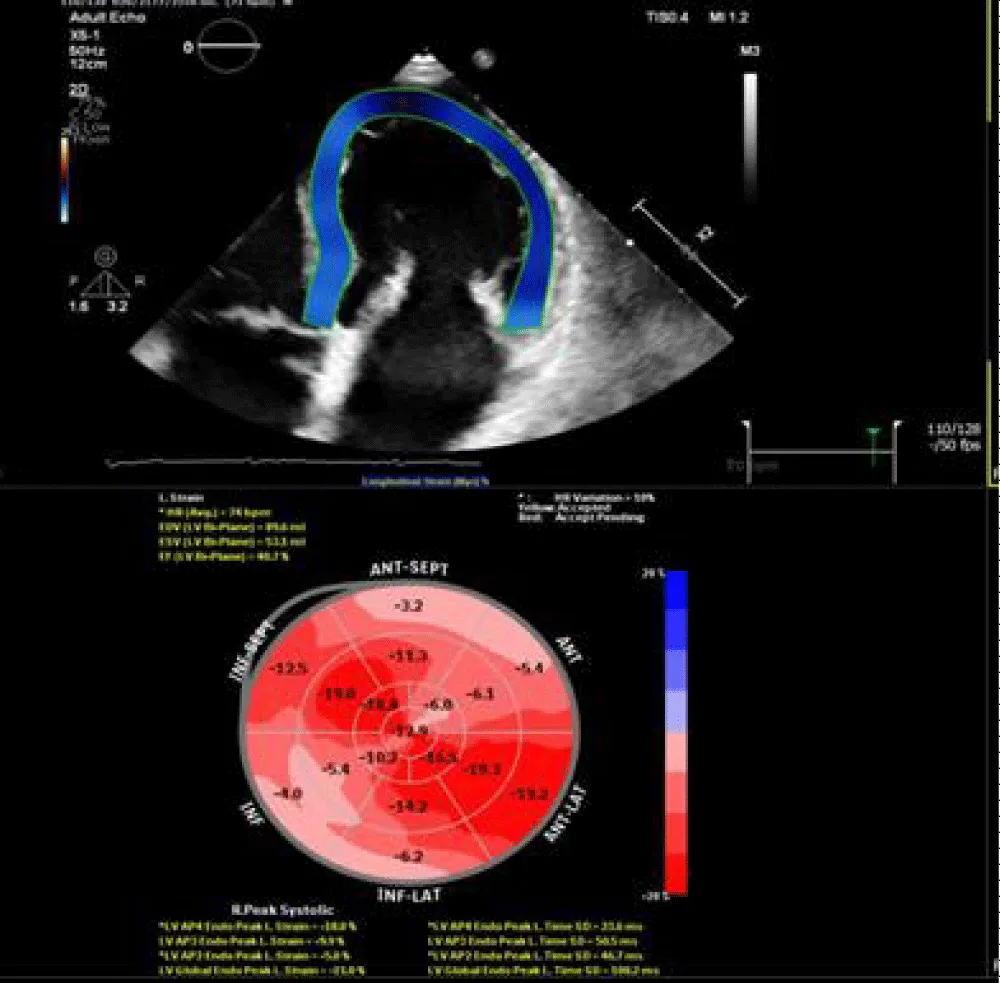

Figure 3: 3D TEE revealed mildly dilated LV volumes with GLS = -19.4%.

Figure 4: CMR-LGE 4 chamber view revealed no fibrosis.

Figure 9: 3D TTE revealed average LV volumes with GLS =-17.2%.

Figure 10: CMR -LGE, 3 chamber view revealed nonterritorial sub-endocardial fibrosis of lateral wall (arrows).